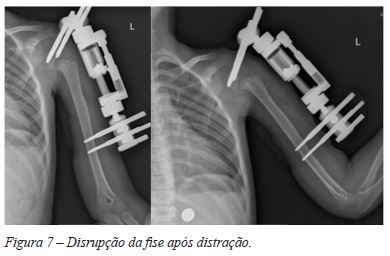

Decorridos 5 meses após o diagnóstico, realizou-se o tratamento cirúrgico, que se desenvolveu em 2 fases distintas. Numa primeira cirurgia, colocou-se um fixador externo com 2 cravos paralelos, revestidos a hidroxiapatite, diâmetro 6mm, a nível da epífise umeral e 2 cravos de diâmetro 4 mm, paralelos, a nível da diáfise, a cerca de 10 cm distalmente à região fisária (Figura 5). O intervalo entre os cravos do mesmo lado foi de 1 cm. De seguida foi aplicado dispositivo de distracção, tendo sido realizada intra-operatoriamente uma distração de cerca 6mm (Figura 6). A distração foi continuada por 13 dias, ao ritmo da 1-1.5mm/dia, até à data em que a doente referiu desconforto súbito a nível do ombro esquerdo, correspondente a fratura-epifisiólise da placa de crescimento do úmero proximal. A radiografia realizada ao 18º dia após o início da distração, atestou a disrupção da fise com uma distração de cerca de 4.6 mm na região lateral da fise umeral proximal (Figura 7). A 2ª fase do tratamento cirúrgico realizou-se 19 dias após a cirurgia inicial. Procedeu-se à extração do fixador externo e cravos. Tendo em conta a existência de tecido de granulação e zonas de endurecimento a nível dos cravos, estas áreas, bem como a zona da biópsia foram incluídos na linha de incisão cirúrgica, que seguiu a linha de planeamento para uma incisão utilitária do membro superior (Figura 8). Fez-se aponevrectomia em linha com incisão cutânea, com identificação e preservação da veia cefálica no sulco delto-peitoral, e identificação do tendão grande peitoral, realizando-se desinserção distal do mesmo após referenciação com margem de segurança (Figura 9). De seguida, identificou-se a curta porção do bicípite e coraco-braquial a nível inserção proximal, procedeu-se à sua desinserção após referenciação. Identificaram-se os nervos musculo-cutâneo, radial e axilar, tendo-se constatado que este último, não se encontrava envolvido na massa de tecidos moles, o que permitiu a sua preservação. Procedeu-se à laqueação selectiva dos vasos nutritivos do tumor. Marcou-se o nível de osteotomia a cerca de 9 cm da extremidade proximal do tumor, seccionando a longa porção do bicípite braquial e parte da inserção deltoide a esse nível.